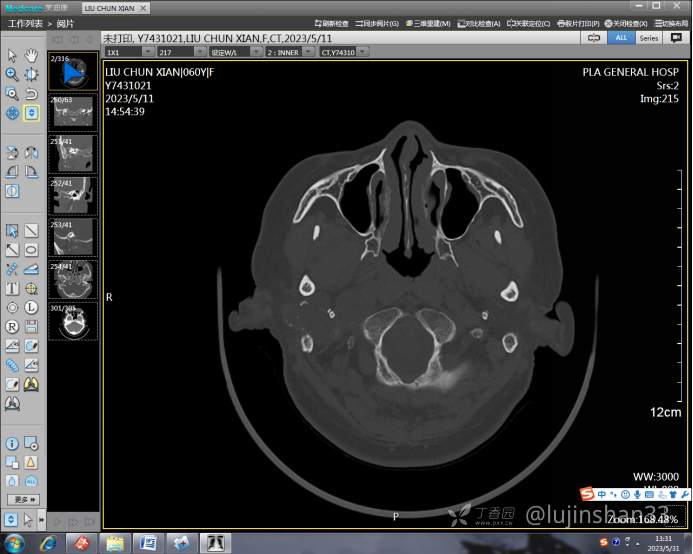

(2023-05-12 10:15,本院)行CT(颅脑)检查提示:右侧颞骨广泛骨质破坏,伴巨大软组织肿块,性质待定,考虑肿瘤性病变,颈静脉球瘤?软骨源性肿瘤?请结合临床及病理进一步明确。